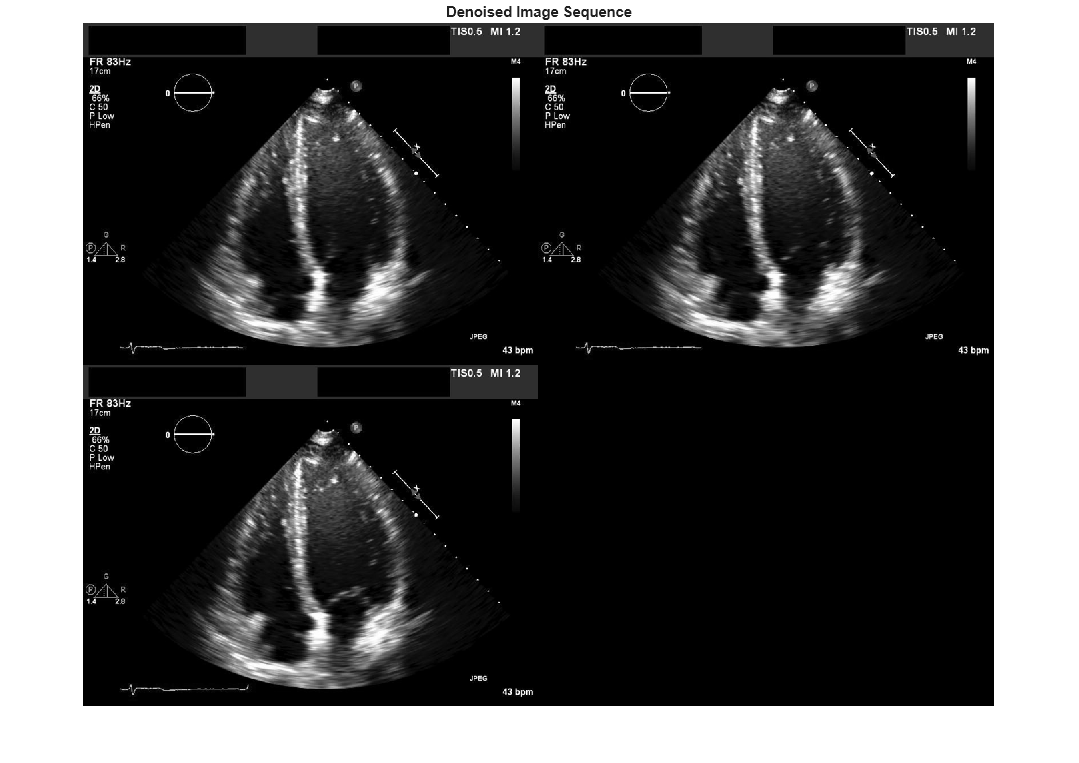

Coherent imaging modalities, such as ultrasound images, are prone to degradation

because of the interference of the transmitted waveform and its echoes. This degradation is

called speckle, and is a form of multiplicative noise. The

specklefilt function uses a speckle-reducing anisotropic diffusion (SRAD)

algorithm to reduce the speckle in an image.

The speckle-reducing anisotropic diffusion used in specklefilt combines

elements of speckle-reducing filters with the edge-preserving anisotropic diffusion filter

used in imdiffusefilt. This makes specklefilt useful for

edge-preserving denoising of images corrupted with speckle.